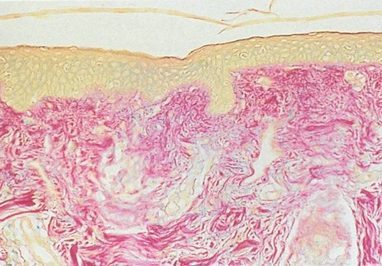

Pharmaceutical skin therapeutics refers to topical skin repair treatments you can apply yourself. Those used in our clinic are of prescription-only strength because of their scientifically-proven mechanism of action and efficacy.

Skin Doctor SA has developed its own skin repair products, based on recent peer-reviewed dermatological, therapeutic and scientific principles.

These products are designed to enhance and maintain the results achieved by our broad range of treatments, but are also very effective in their own right as agents of skin rejuvenation and repair.